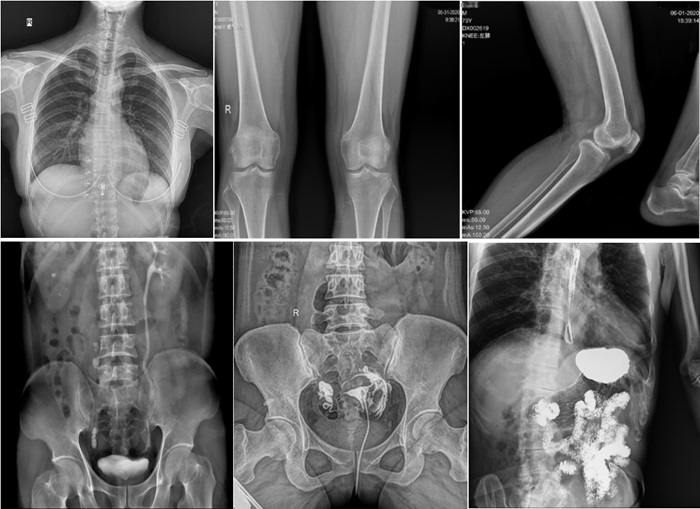

在實(shí)際應(yīng)用中,普利德動(dòng)態(tài)平板DRF展現(xiàn)出了多種優(yōu)勢。例如,在胸部影像檢查中,它清晰顯示肺部紋理和結(jié)節(jié),為肺癌早期篩查提供有力支持;在骨科領(lǐng)域,可用于骨折的診斷和復(fù)位效果評(píng)估,幫助醫(yī)生制定更精準(zhǔn)的治療方案;在消化系統(tǒng)檢查中,能有效發(fā)現(xiàn)胃腸道疾病的異常。